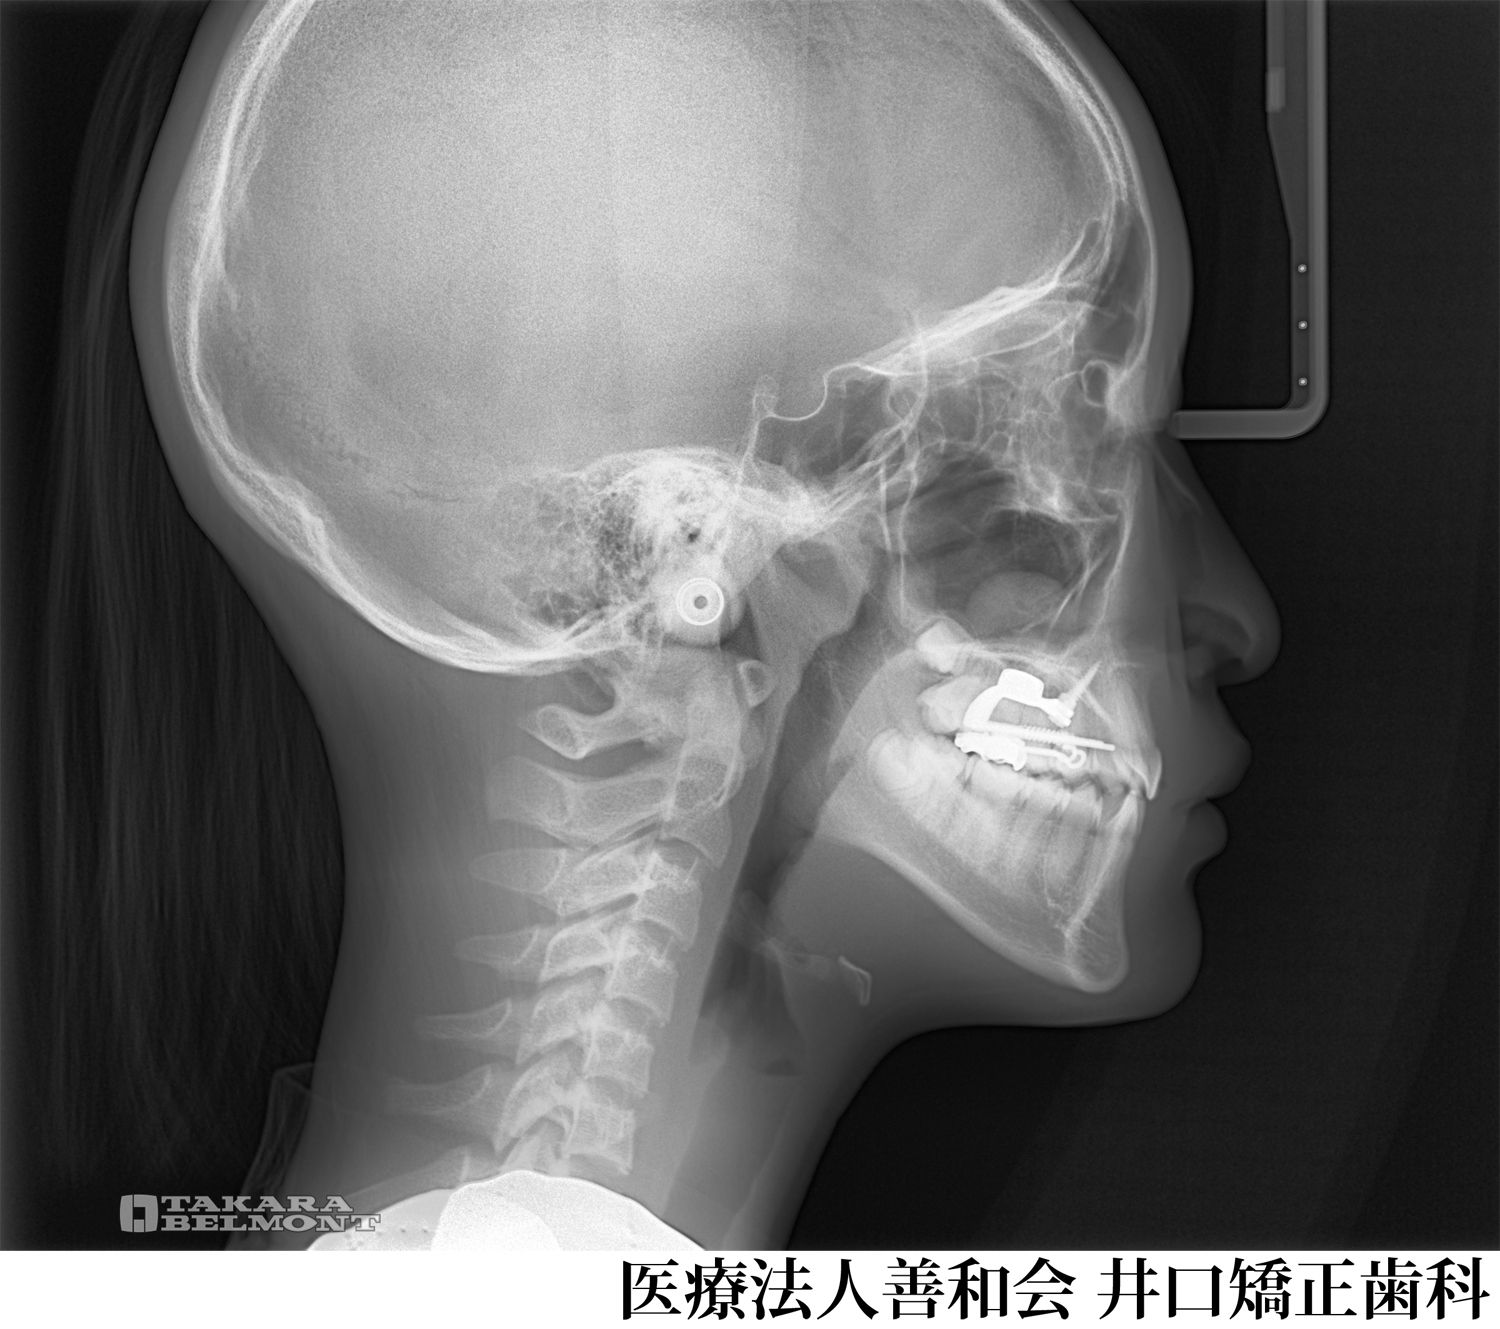

¡Ú¾ÉÎã2¡Û¥Þ¥¦¥¹¥Ô¡¼¥¹·¿¥«¥¹¥¿¥à¥á¥¤¥É¶ºÀµÁõÃ֤Ǽ£ÎŤò¹Ô¤Ã¤¿À®¿Í¶ºÀµ¤Î¾ÉÎã(¥¤¥ó¥Ó¥¶¥é¥¤¥ó»ÈÍÑ)

- ¼£ÎÅÁ°

- ¼£ÎŸå

- ¼£ÎÅ̾

- ¥Þ¥¦¥¹¥Ô¡¼¥¹·¿¥«¥¹¥¿¥à¥á¥¤¥É¶ºÀµÁõÃ֤Ǽ£ÎŤò¹Ô¤Ã¤¿À®¿Í¶ºÀµ¤Î¾ÉÎã(¥¤¥ó¥Ó¥¶¥é¥¤¥ó»ÈÍÑ)

- ½é¿Ç»þǯÎð:21ºÐ ½÷À

¼£ÎÅÆâÍÆ

´µ¼ÔÍͤξɾõ

±ü»õ¤Î°ÌÃÖ´Ø·¸¤Ï´ð½à¤È¤Ê¤ë¤È¤³¤í¤«¤é¼õ¤±¸ýÊý¸þ¤Ë¥º¥ì¤Æ¤ª¤ê¡¢Á°»õ¤Î³ú¤ß¹ç¤ï¤»¤Ï·ÚÅÙ¤ÎÈ¿ÂÐÒû¹ç¤È¤Ê¤Ã¤Æ¤¤¤¿¡£

¾å¤ÎÁ°»õ¤ËÁÑÀ¸(»õ¤Ê¤é¤Ó¤Î¥¬¥¿¥¬¥¿)¤òǧ¤á¡¢¤Þ¤¿¿âľŪ¤Ë¤â³«Òû¤È¤Ê¤Ã¤Æ¤¤¤¿¡£ -

¼£ÎÅË¡

-

¥Þ¥¦¥¹¥Ô¡¼¥¹·¿¥«¥¹¥¿¥à¥á¥¤¥É¶ºÀµÁõÃÖ¤ò»ÈÍѤ·¡¢ÈóÈ´»õ¤ÇÇÛÎó¤ò¹Ô¤¤¤Þ¤·¤¿¡£

¼£ÎÅ·ë²Ì

±±»õ´Ø·¸¤Î¥º¥ì¡¢Á°»õ¤ÎÈ¿ÂÐÒû¹ç¡¢³«Òû¤Ï²þÁ±¤·¤Þ¤·¤¿¡£